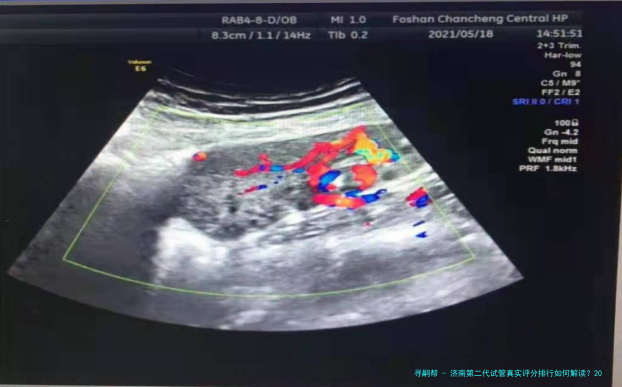

选择第二代试管(ICSI)医院时,单精子注射技术的成熟程度与胚胎培育试验室等级直接影响性价比。下列是济南地区主流医院的综合数据相比较:

第二代试管费用高于代,因增加了单精子注射环节。2025年济南地区样板费用构成如下:

取卵与单精子注射:20000-30000元(含ICSI操作费)

核心问题:第二代试管比代贵在何处?